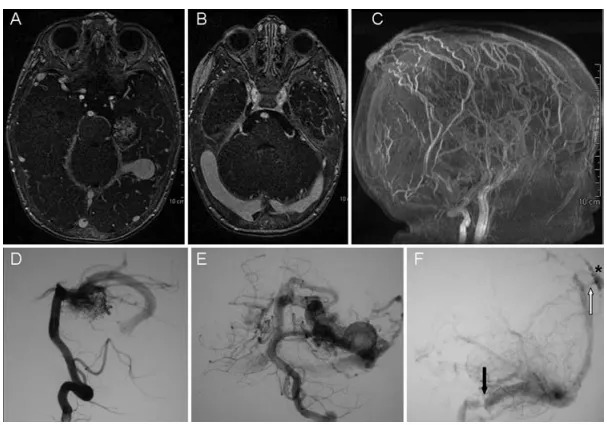

神经影像学研究:鉴于上述临床表现,决定进行深入的影像学检查,以探究皮肤肿胀、巨头畸形和静脉淤血之间的潜在联系。随后进行的脑部血管磁共振成像检查,发现存在脑血管畸形,包括一个位于左侧颞叶内侧的动静脉畸形、弥漫性的颅内和颅外静脉扩张,以及一个巨大的静脉“动脉瘤”(图2)。脑血管造影进一步证实存在一个直径1.8厘米的颞叶动静脉畸形病灶,该病灶由左侧大脑后动脉供血,并伴有弥漫性颅内静脉扩张。然而,左侧乙状窦可见局灶性锯齿状狭窄,从而导致横窦和上矢状窦的反向充盈,并使得从该窦引流的颅外静脉发生扩张。

图2.脑部血管磁共振成像检查。可清晰显示颞叶内侧病灶及静脉动脉瘤,右侧横窦扩张,以及扩张的皮下静脉。椎动脉造影侧位及正位像显示由左侧大脑后动脉颞支供血、经一条显著扩张的静脉引流的动静脉畸形。可见邻近横窦的巨大静脉动脉瘤,乙状窦闭锁,以及由此导致的血流经一条导静脉反流入上矢状窦和颅外皮下循环。